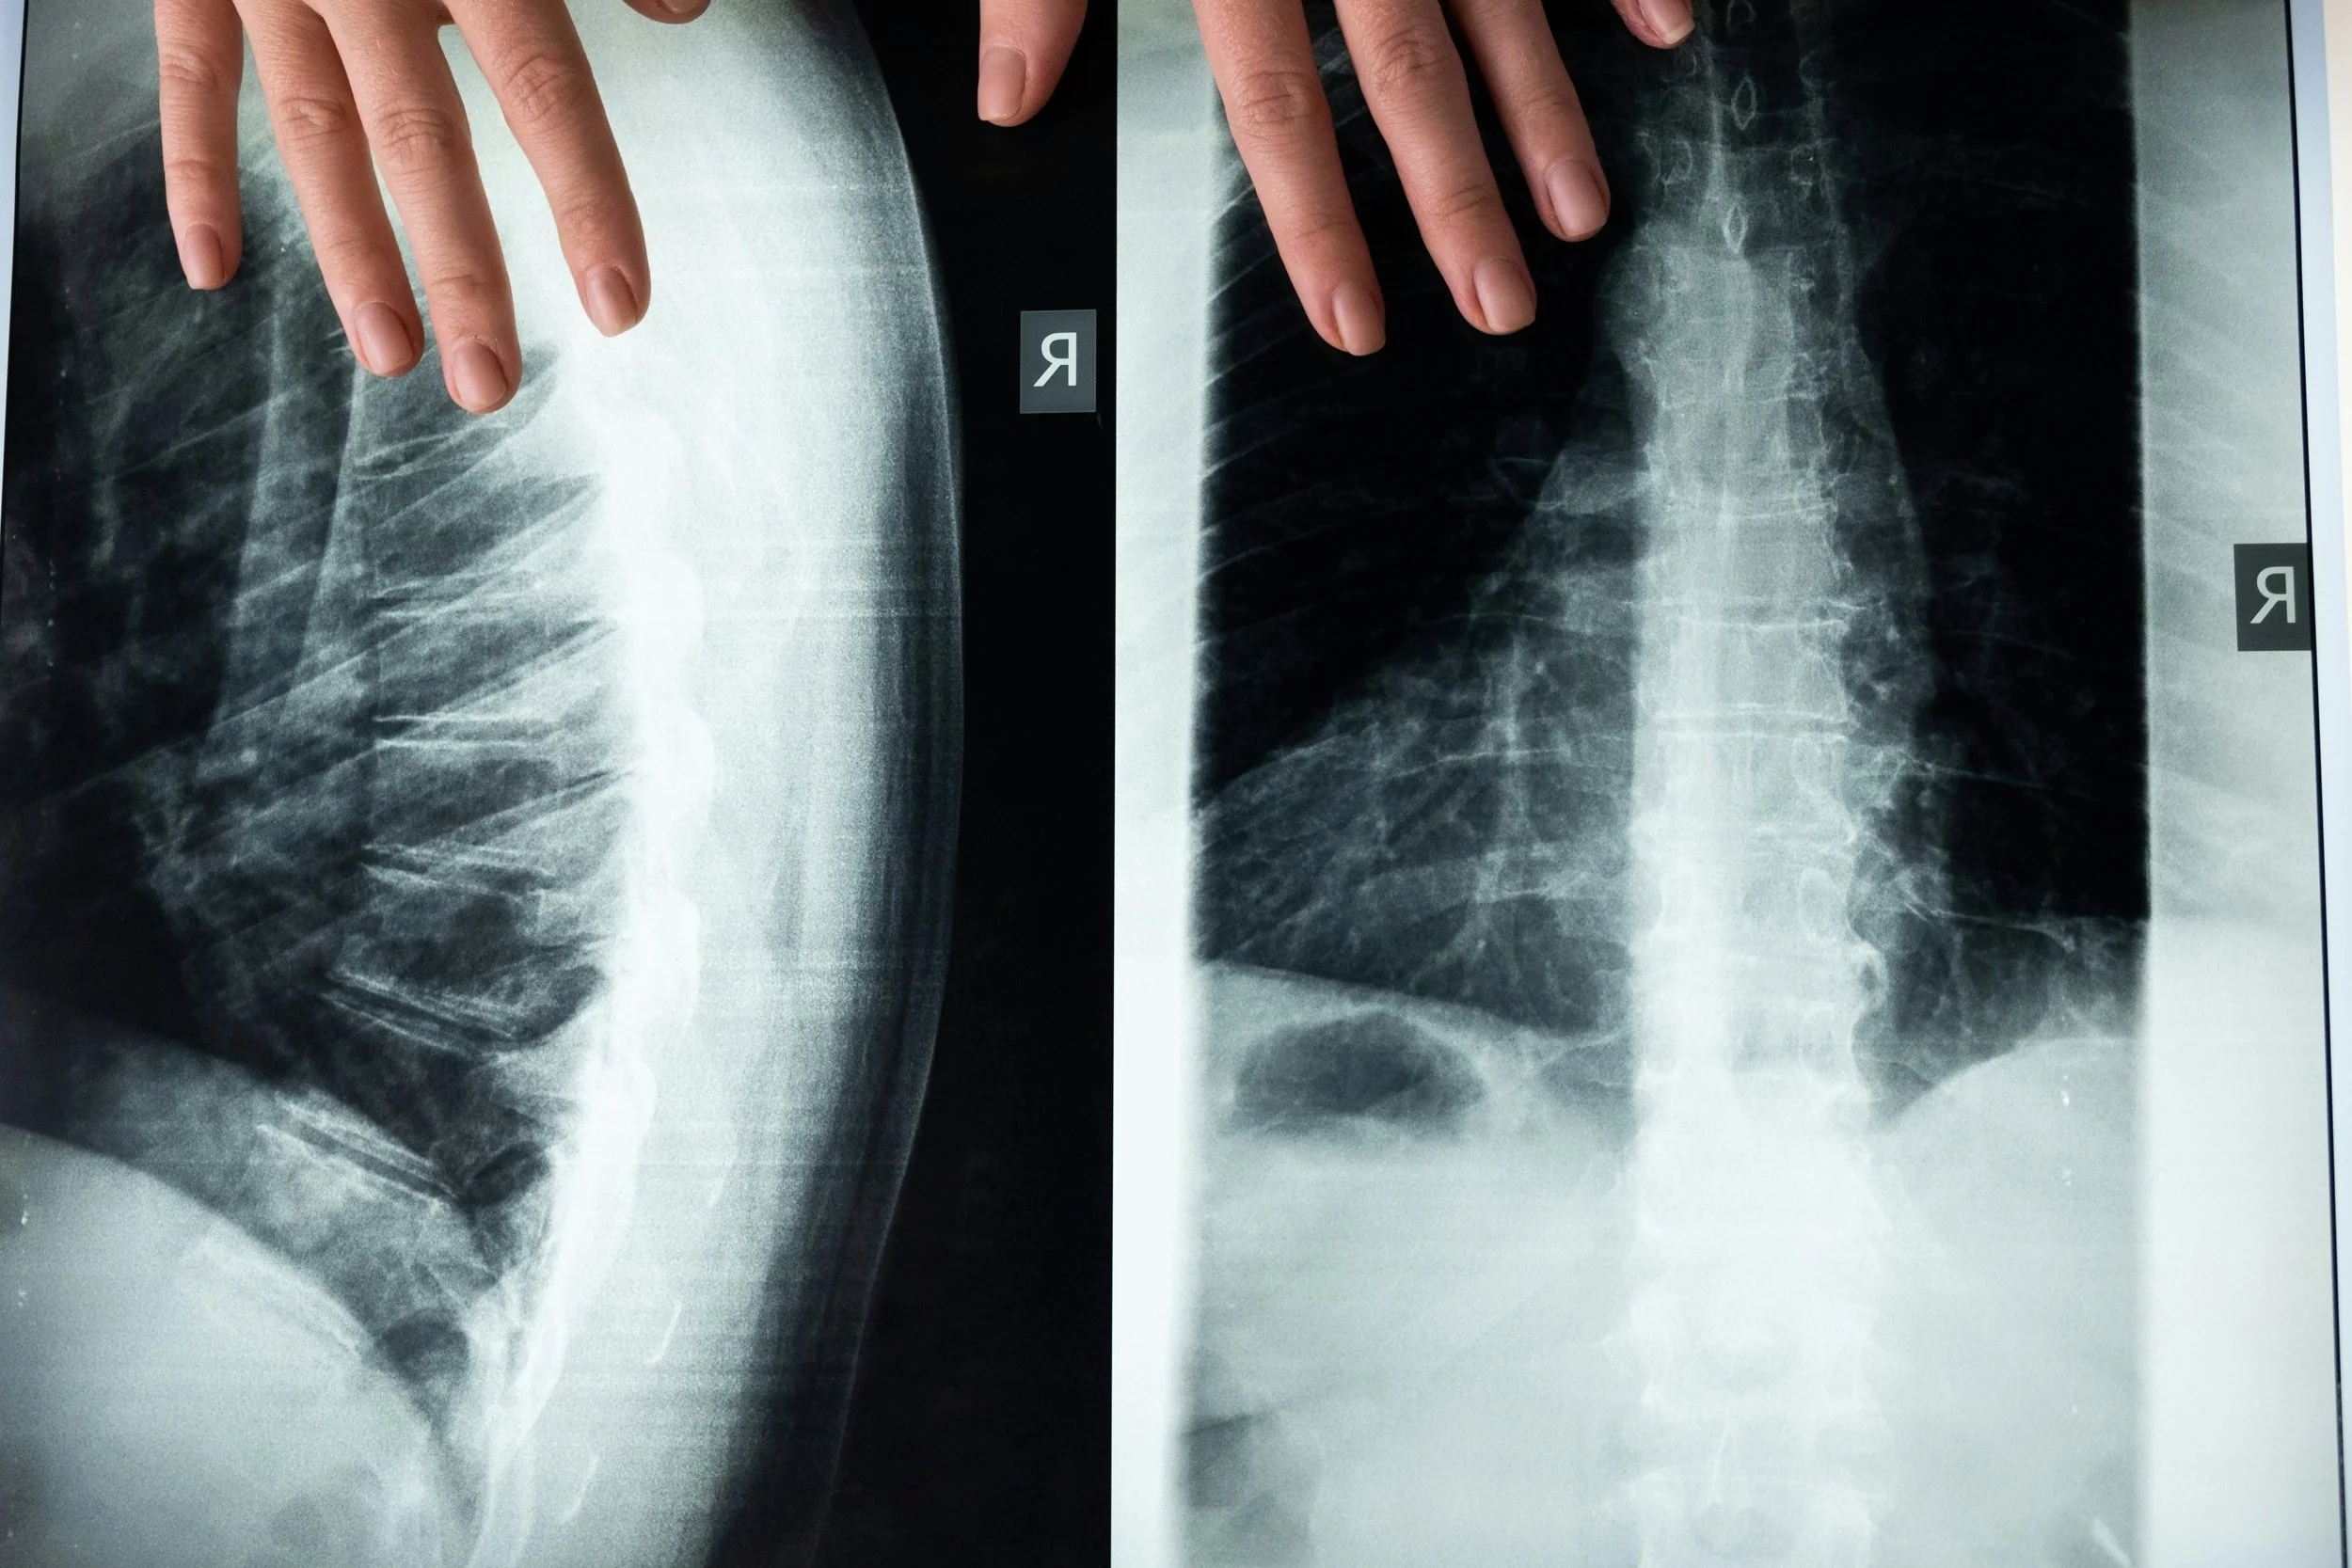

Minimally Invasive Deformity Surgery for Scoliosis

This surgical approach is to correct spinal curvature (scoliosis) using smaller incisions (versus traditional), muscle-sparing techniques, and specialized instrumentation. The surgery involves detailed imagery (x-ray, MRI, CT) to measure the spinal curves, identify rigid segments, and plan the screw placement. The patient is placed in a prone position on a radiolucent table with access to the spine .A small incision is made to the affected vertebrae, using specialized instruments and retractors to gently move muscles. Pedicle screws are inserted into the vertebrae, and rods are placed for the instrumentation segments, stabilizing the spine permanently. Incisions are then closed with minimal tissue disruption to reduce scarring and postoperative pain.

-

This surgery is done when conservative management with PT, medications and injections fail to resolve back and leg pain. It is done for adult and degenerative scoliosis and adolescent idiopathic scoliosis.

The include smaller incision, less tissue trauma, faster recovery and shorter hospital stay, reduced blood loss, effective correction and spinal stabilization, lower risk of infection and complications, and preservation of surrounding muscles and ligaments.

Typical hospital stay is 3-5 days, depending on the number of levels addressed. Patients begin walking the day after surgery. Physical therapy is initiated within a few weeks to restore strength and flexibility. Light activities can be resumed within 4-6 weeks, and more strenuous activity over 3-6 months. The fusion timeline is generally 6-12 months. Physician follow-up is needed to ensure proper hardware placement and spinal alignment.

Minimally Invasive Posterior Lumbar Fusion: Transforaminal Lumbar Interbody Fusion (TLIF)

The minimally invasive procedure involves removing damaged discs between the vertebrae and fusing the vertebrae to stabilize the spine. The "transforaminal" part of the name refers to the surgical approach, which accesses the spine through the posterolateral region, the side, in an area called Kambin's Triangle, or the "foramen,” to minimize disruption to surrounding tissues like muscles and nerves. During a TLIF, the surgeon will remove the affected disc material and replace it with a bone graft and spacer (Cage) to help the vertebrae fuse over time, in addition to screws and rods.

TLIF is done for patients with degenerative disc disease, spondylolisthesis, spinal stenosis, herniated discs, and spinal instability. TLIF is considered when non-surgical treatments (such as physical therapy, medications, or injections) have not provided sufficient relief, and surgery is necessary to improve stability and reduce pain.

This surgery reduces abnormal motion at a degenerated or unstable disc level and decreases pain and nerve compression. It further reduces degeneration of the surrounding segments, restores disc height, can reduce mild spinal deformities, and protects the spinal nerves from irritation and compression. The TLIF approach from the posterior minimizes surgical trauma to spinal muscles and ligaments compared to a traditional posterior fusion: less blood loss, smaller incision, and less postoperative muscle trauma. The surgical approach also allows direct access to the disc space and spinal canal. It preserves midline bony structures and ligaments, and maintains spinal integrity and reduces post op pain. The procedure can be done at a single or multiple levels

Most patients will undergo a Minimally Invasive TLIF (MIS TLIF) at an outpatient facility and go home the same day. Depending on medical comorbidities, some surgeries may be done in the hospital and require an overnight stay. Some patients may be instructed to wear a back brace to support the spine during the early stages of recovery. Expect some pain and discomfort after surgery, but medications will help manage this. Your doctor will guide you on transitioning off stronger medications. Physical therapy may be prescribed after a few weeks, and walking is recommended within the first few days. In the short term, sitting for periods longer than 30 minutes is discouraged, as is bending, lifting, and twisting. Full recovery can take up to 6-12 months for the fusion to solidify.